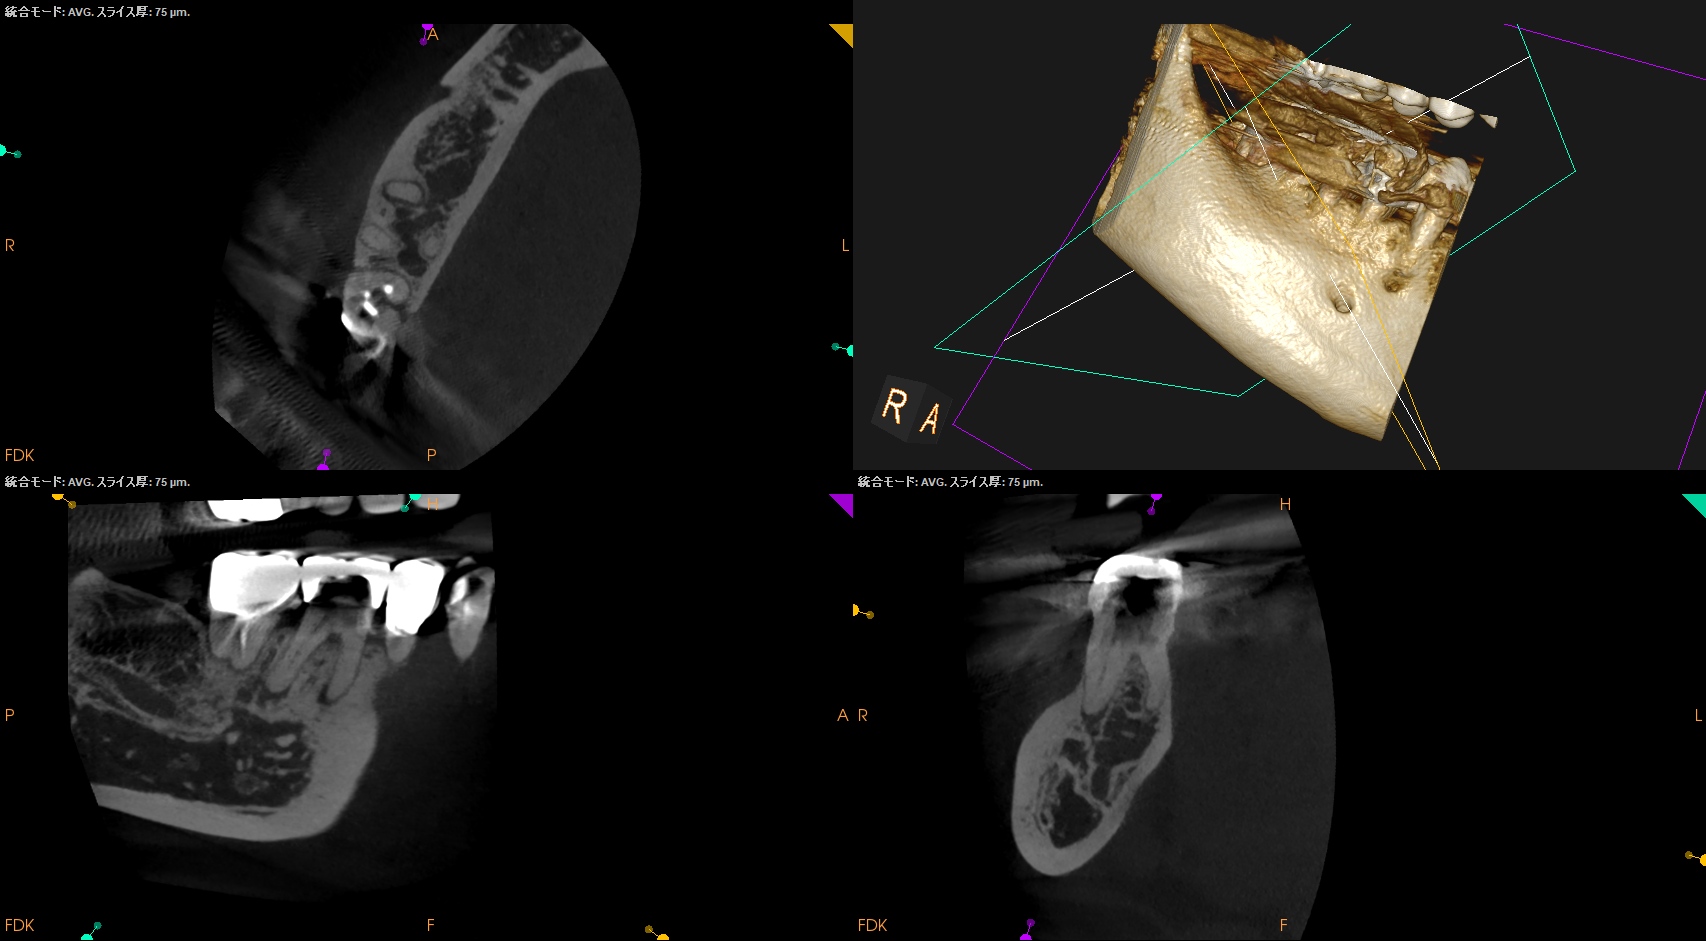

Pre-op Endo test(2026.3.11)

MB

ML

D

Radix

Gold Inlayの封鎖性を持ってしても歯髄の生活性を担保することはできなかったようだ。

ということでRadix以外の根管全てに根尖病変があり、穿通がマストだ。

が、歯髄に近い修復で石灰化が進んでいる。

SXを入れる前に短針でスカウティングが必要だろう。

またRadixも湾曲が強い。

ここも形成で工夫が必要だ。

Pulp Dx: Pulp Necrosis

Periapical Dx: Symptomatic apical periodontitis

Recommended Tx: RCT